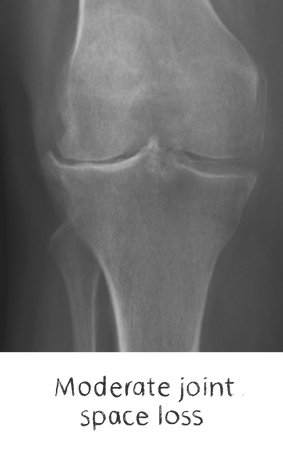

Generally, they all tend to lead to degeneration of the joint, with loss of cartilage, variable bone loss, deformity, stiffness, swelling, and most importantly – PAIN. We commonly call this group – degenerative joint disease

Plain film x-rays are taken to assess the joint

These are usually taken prior to your appointment. These help to confirm the diagnosis, assess the wear pattern and look for particular deformities. They can show old metalware and its position in the bone.